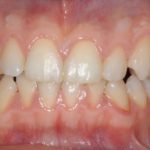

Trattamento dell’affollamento nella dentatura mista

The relieving of crowding in the mandibular arch in the mixed dentition

Una malocclusione che non si autocorregge, anzi tende a peggiorare nel tempo: l’articolo...